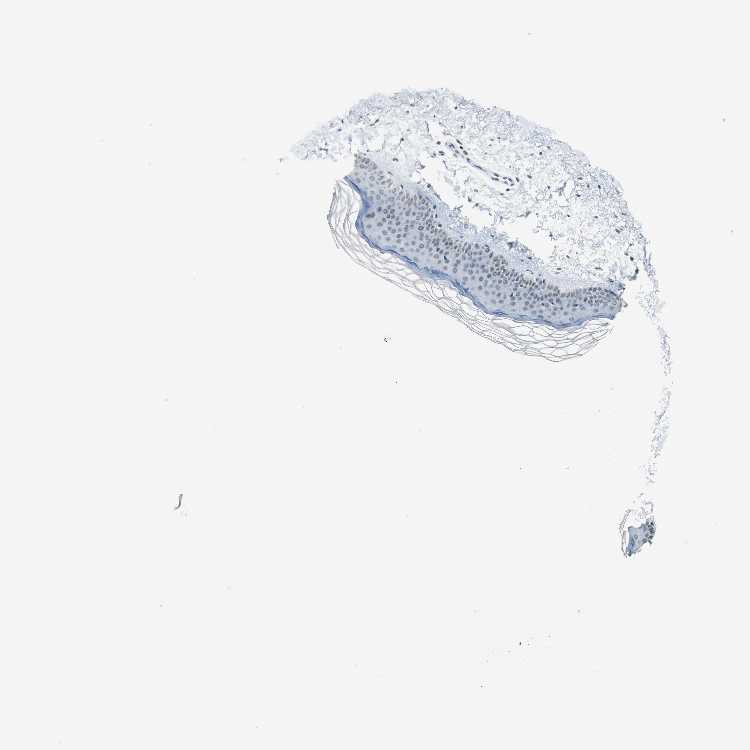

SKIN 1 - Antibody stainingi

Antibody staining in the annotated cell types in the current human tissue is reported as not detected, low, medium, or high, based on conventional immunohistochemistry profiling in selected tissues. This score is based on the combination of the staining intensity and fraction of stained cells.

Each image is clickable and will lead to virtual microscopy that enables deeper exploration of all samples and also displays staining intensity scores, fraction scores and subcellular localization as well as patient and tissue information for each sample.

Antibody HPA052052Antibody CAB005583Antibody CAB072336

Langerhans Not detectedNot detectedNot detected

Fibroblasts MediumLowNot detected

Keratinocytes MediumNot detectedNot detected

Melanocytes MediumNot detectedNot detected

SKIN 2 - Antibody stainingi

Epidermal cells MediumNot detectedNot detected